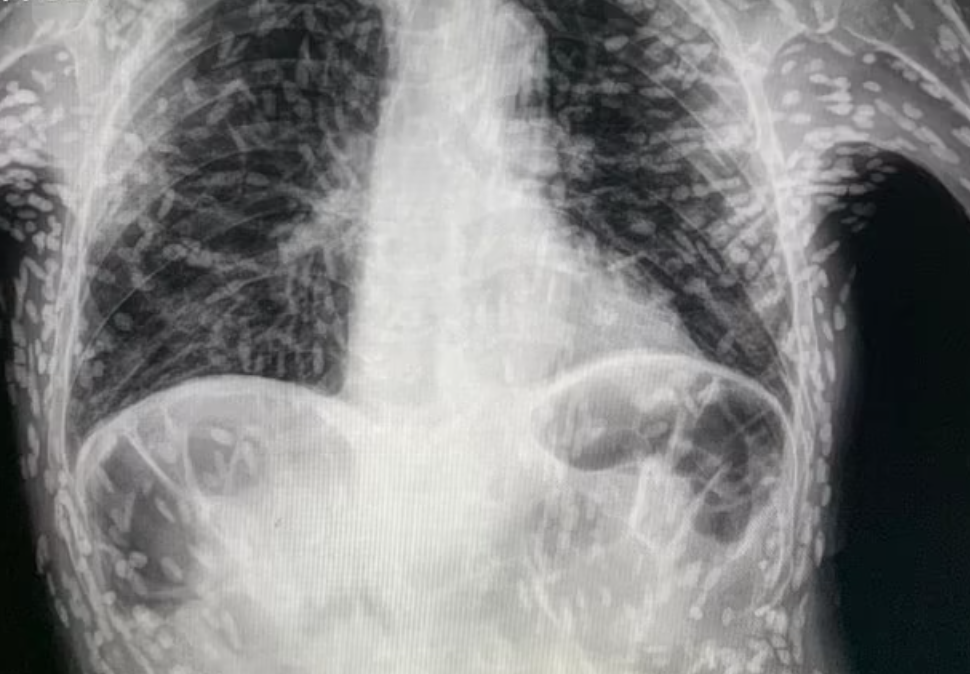

أظهرت صور أشعة سينية مرعبة جسد رجل مليئًا ببيض الدودة الشريطية بعد خطأ حيوي في المطبخ أدى إلى غزو طفيلي.

وبمجرد تناولها، تشكل الديدان الشريطية أكياسًا متكلسة صلبة أو بيضًا ميتًا “زومبيًا” يمكن أن تشعر وكأنها كتل تحت الجلد، وتظهر مثل “حبة الأرز” في الفحوصات الطبية.

وفي الصورة التي شاركها الدكتور غالي، يمكن رؤية حوض رجل مرقط بمئات من هذه الأكياس المتكلسة.

أوضح الدكتور غالي أن اليرقات غير ضارة بشكل عام، ويرجع ذلك جزئيًا إلى أنها لا تنجو خارج الأمعاء. ومع ذلك، يمكن أن تسبب الأكياس مشاكل إذا تطورت في الدماغ.